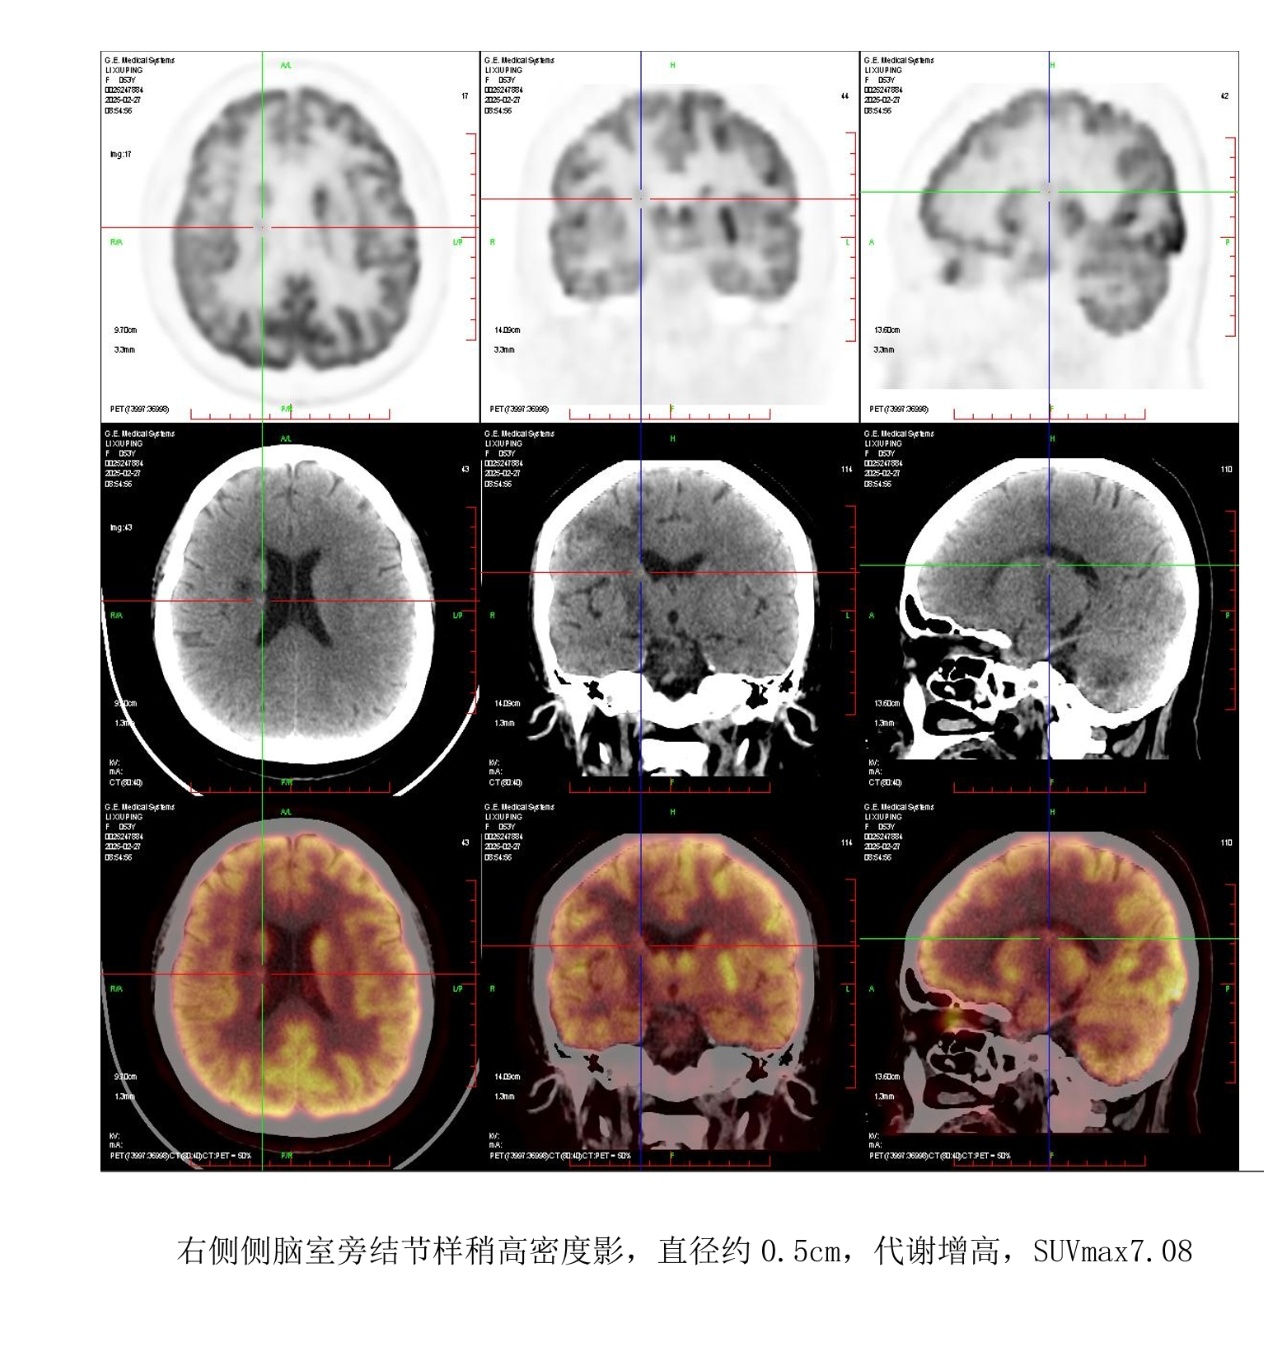

四个疗程RMO方案后显示病灶0.8*0.8 suv 7.1

还有这两个是高代谢

还有两个0.5的高代谢,我看都在灰质附近有没有可能本来就是高代谢的地方,大神帮忙看看